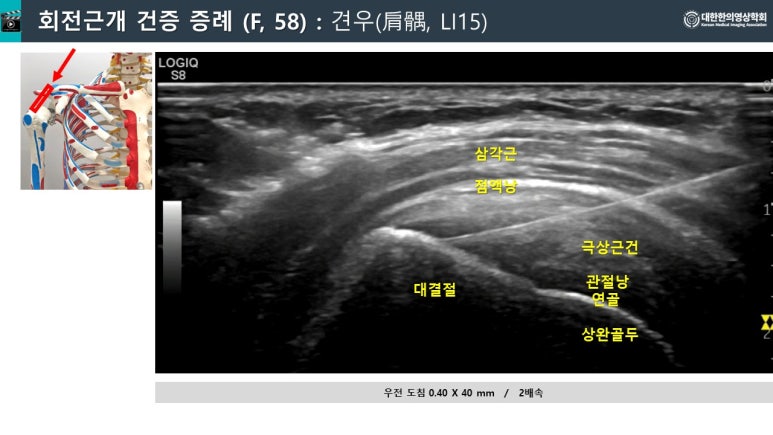

​안녕하세요​미국진단초음파협회 자격자 모임​한의초음파연구회 부회장안태석 원장​입니다.​​오늘 영하15도로 추운 날씨에도많은 분들께서 내원해주셨는데​그 중 어깨 회전근개 파열이5 케이스나 되네요. ​​그래서 오늘은 ​어깨 회전근개 수술을 결정하는 <판단 기준>과 ​​<VARO 비수술요법>으로성공적으로 치료되었던 ​회전근개 케이스들을 소개해드리고자 합니다. ​